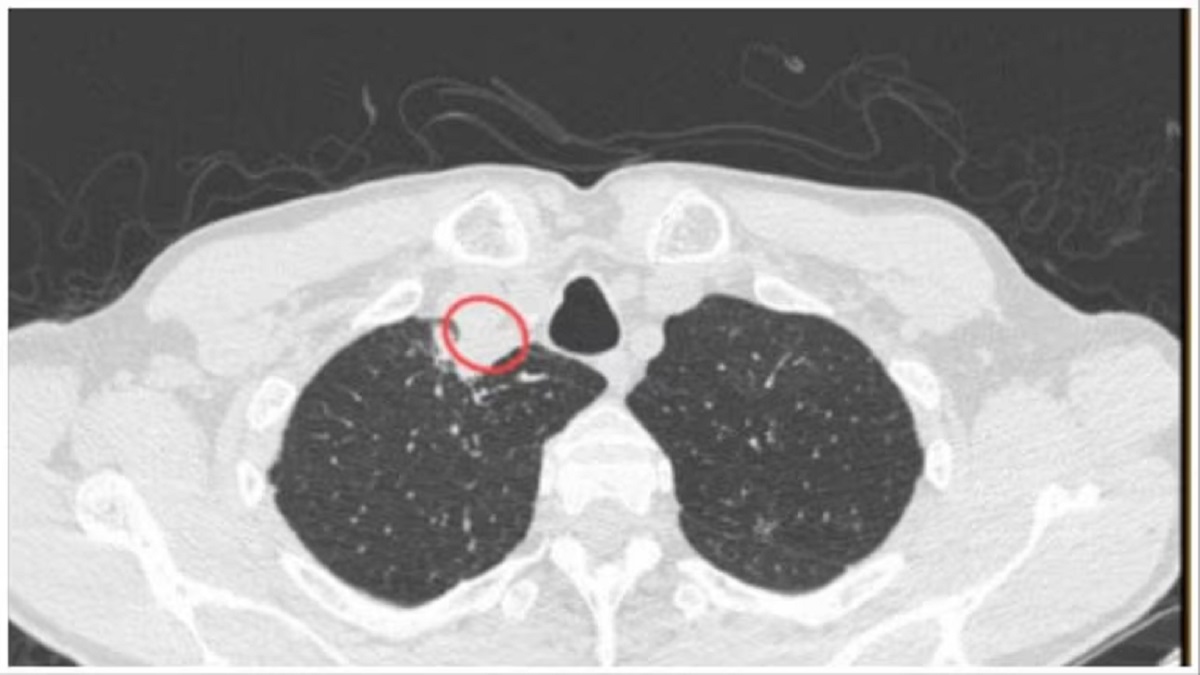

गर्दन के सीटी स्कैन में खतरनाक फोड़ा आया सामने

रोगी की गर्दन के सीटी स्कैन से पता चला कि दाहिना पैराट्रैचियल फोड़ा मौजूद है। डॉक्टरों ने रोगी में गर्दन में फोड़ा का पता लगाया और शल्य चिकित्सा से इसे निकाल दिया। इसके बाद, रोगी को एंटिफंगल दवा का एक कोर्स दिया गया और दो साल के नियमित फॉलो-अप के बाद उसे फिट घोषित किया गया।